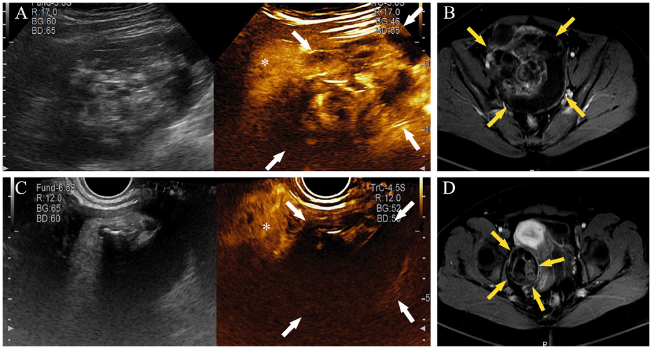

共纳入46例不确定性盆腔肿块患者,其中3例因临床病史及多种检查资料怀疑是输卵管炎症,临床采取保守抗炎治疗后临床症状好转或消失,出院后6个月内复查超声显示包块明显缩小或消失;其余43例行手术切除后均取得术后病理。良性病灶共24例,患者年龄(44.5±13.2)岁;恶性病灶共22例,患者年龄(53.6±11.0)岁,见表1。1例典型病例的CEUS及MRI增强扫描图像资料如图1所示。

图1 一例盆腔肿块患者的CEUS和MRI增强扫描检查结果

注:患者31岁,健康体检发现盆腔包块8月余,术前检测肿瘤标志物CA125 205 U/L,CA199 524.3 U/L,HE4 36.1 pmol/L,AFP 8.73 ng/mL,左侧附件肿块为未成熟畸胎瘤,右侧附件肿块是成熟畸胎瘤。A为CEUS结果,示左侧附件区囊实性肿块,CEUS 24 s 肿块内部不均匀增强(白色箭头),增强程度高于子宫肌层(*);B为MRI T1增强扫描轴位结果,示左侧附件区不均匀增强的囊实性肿块(黄色箭头);C为CEUS结果,示右侧附件区囊实性肿块,CEUS 24 s 肿块内部不均匀增强(白色箭头),增强程度低于子宫肌层(*);D为MRI T1增强扫描轴位结果,示右侧附件区不均匀低增强的囊实性肿块(黄色箭头)。